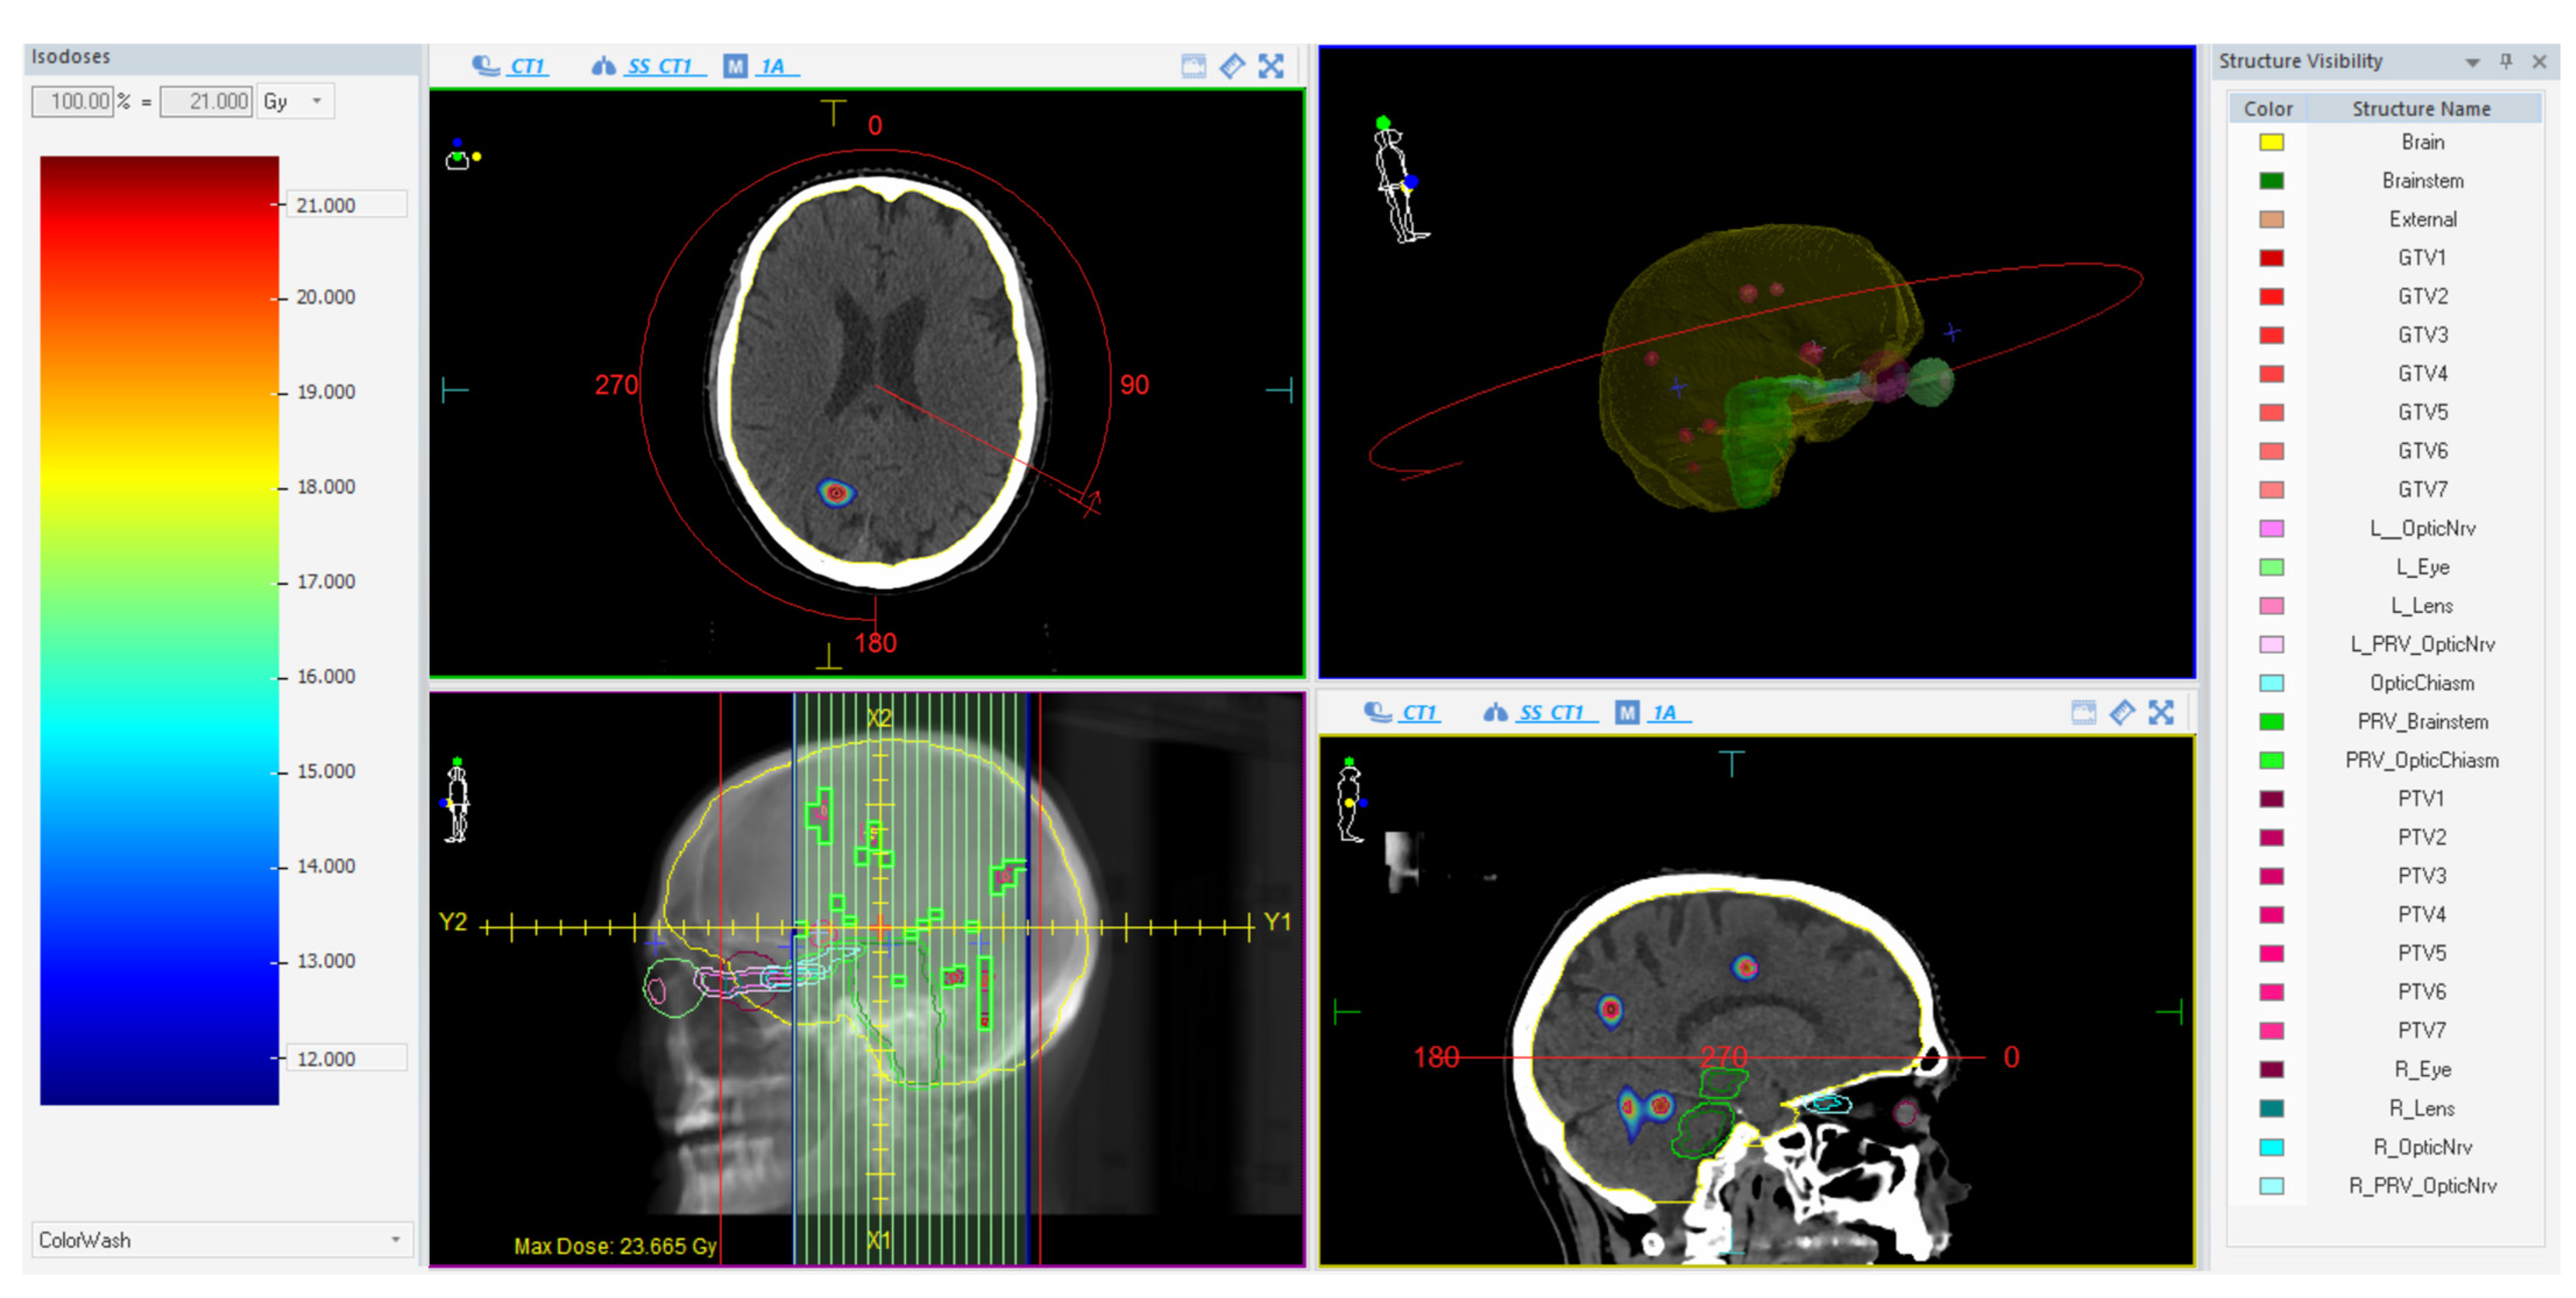

Treatments were planned on a VersaHD linear accelerator (Elekta AB, Stockholm, Sweden) using a single-isocenter VMAT technique with multiple 6 MV flattening-filter-free (FFF) coplanar arcs. The extension and number of arcs for each plan were tailored according to the unique characteristics of the lesions. The Monte Carlo algorithm (1 mm grid spacing and 0.5% statistical uncertainty for calculation) of the treatment planning system (TPS) Monaco (Elekta AB, Stockholm, Sweden) was used for all plans. Prescribed doses were 15–21 Gy in 1 fraction (n = 59) and 27 Gy in 3 fractions (n = 11), as per current guidelines [11,50] depending on the size, the location, and the total volume of BM. All lesions were optimized to have 99% of the PTV surrounded by at least 80% of the prescribed dose and a dose gradient up to 110–115% inside the GTV. In case of target-organs at risk (OARs) overlap, the sparing of the OAR was always prioritized over full target coverage. An illustrative example of a treatment plan is reported in Figure 1.

Figure 1. Illustrative example of a treatment plan using one almost-full single arc with a 90° collimator.